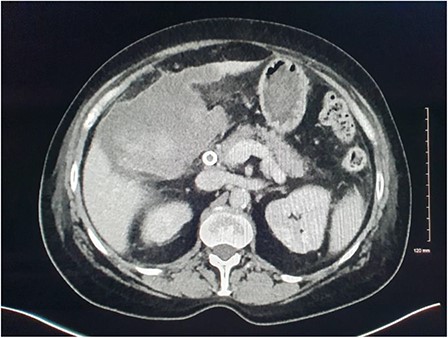

She presented on this occasion with right upper quadrant pain and collapse. Computed tomography (CT) abdomen and pelvis with intravenous contrast in the portal venous phase was performed, demonstrating perforated acute calculous cholecystitis and active haemorrhage (Fig. 1). At this point, Interventional Radiology and Upper gastrointestinal (GI) Surgery in our institution were contacted, and the patient was transferred for emergency embolization. The patient was haemodynamically unstable, so the massive transfusion protocol was commenced.

CT abdomen and pelvis with intravenous contrast in the portal venous phase was performed demonstrating perforated acute calculous cholecystitis and active haemorrhage.